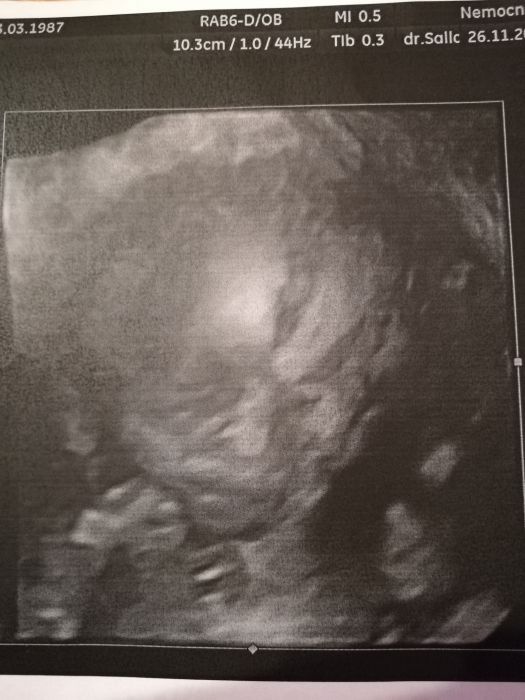

Autor: Erika87 27.11.2018 v 05:27

Holky dekuju, mne 3d delali uz na prvnim screeningu, chodim na nej do nemocnice, tam mi daji obrazek automaticky, jeste pujdeme v tom 30tt. Tohle je z toho prvniho screeningu